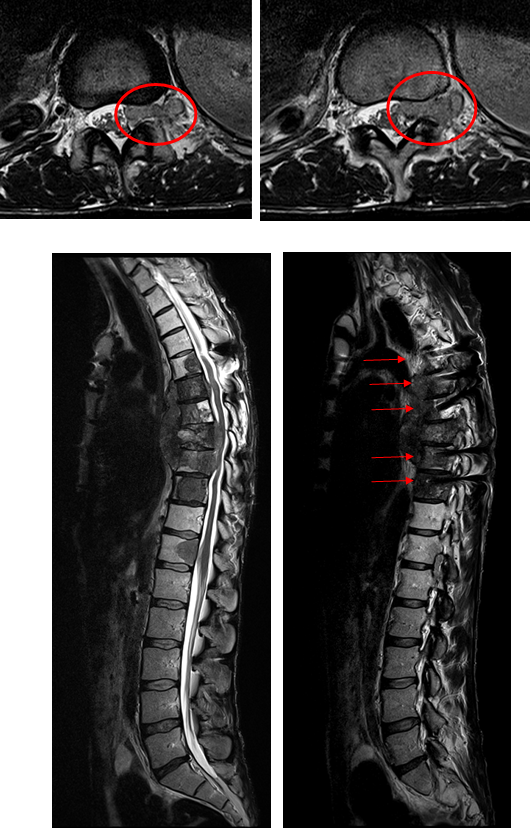

Tim 4G神经系统临床应用

Tim 4G高密度一体化头颈线圈提供高分辨率头部成像,更多的线圈单元数支持更高的iPAT并行采集因子,有利于减少EPI序列的磁敏感伪影。

CASE 3: 胸椎肿瘤(金属植入物)